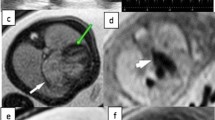

In Scan 1, we observed no infarct on the LGE images of the three infarcted fetuses that underwent LGE CMR. However, LGE images from Scan 2 revealed clear hyper-enhancement of the infarct site in four of the five (80%) infarcted fetuses (Fig. 2b and c). These fetuses were correctly identified as having an infarct in the territory corresponding to the artery that was ligated. No sham fetus underwent LGE CMR in Scan 1. In Scan 2, the LGE images showed no infarction in one of the five infarcted fetuses; however, the quality of the LGE images of this fetus was poor. No hyper-enhanced MI area was seen in the sham fetus that underwent LGE CMR (n = 1) in Scan 2. This sham fetus was therefore correctly identified as having no infarct. Thus, LGE imaging is useful for detecting MI three days after the surgery, but not immediately after the surgery.

Examples of EGE and LGE images of an infarcted heart. a EGE images of the myocardial infarction site seen at Scan 1 and b LGE images of the myocardial infarction site seen at Scan 2 in the same fetus. c A schematic of the LGE image with maternal and fetal structures labeled. Arrows indicate the infarct site

EGE imaging of the myocardial infarct

In Scan 1, two of the four (50%) infarcted fetuses that underwent EGE imaging showed hypoenhancement at the infarct site on the EGE images. The sham fetus had non-diagnostic EGE images due to excessive artefact. In Scan 2, no hypoenhancement could be seen in the EGE images in either the sham (n = 1) or the infarcted fetus (n = 1; Fig. 2a). The EGE images of another infarcted fetus were of unacceptable image quality and the infarct was therefore not identified. These results indicate that EGE imaging is not currently reliable for detecting MI, either immediately or three days after the surgery.